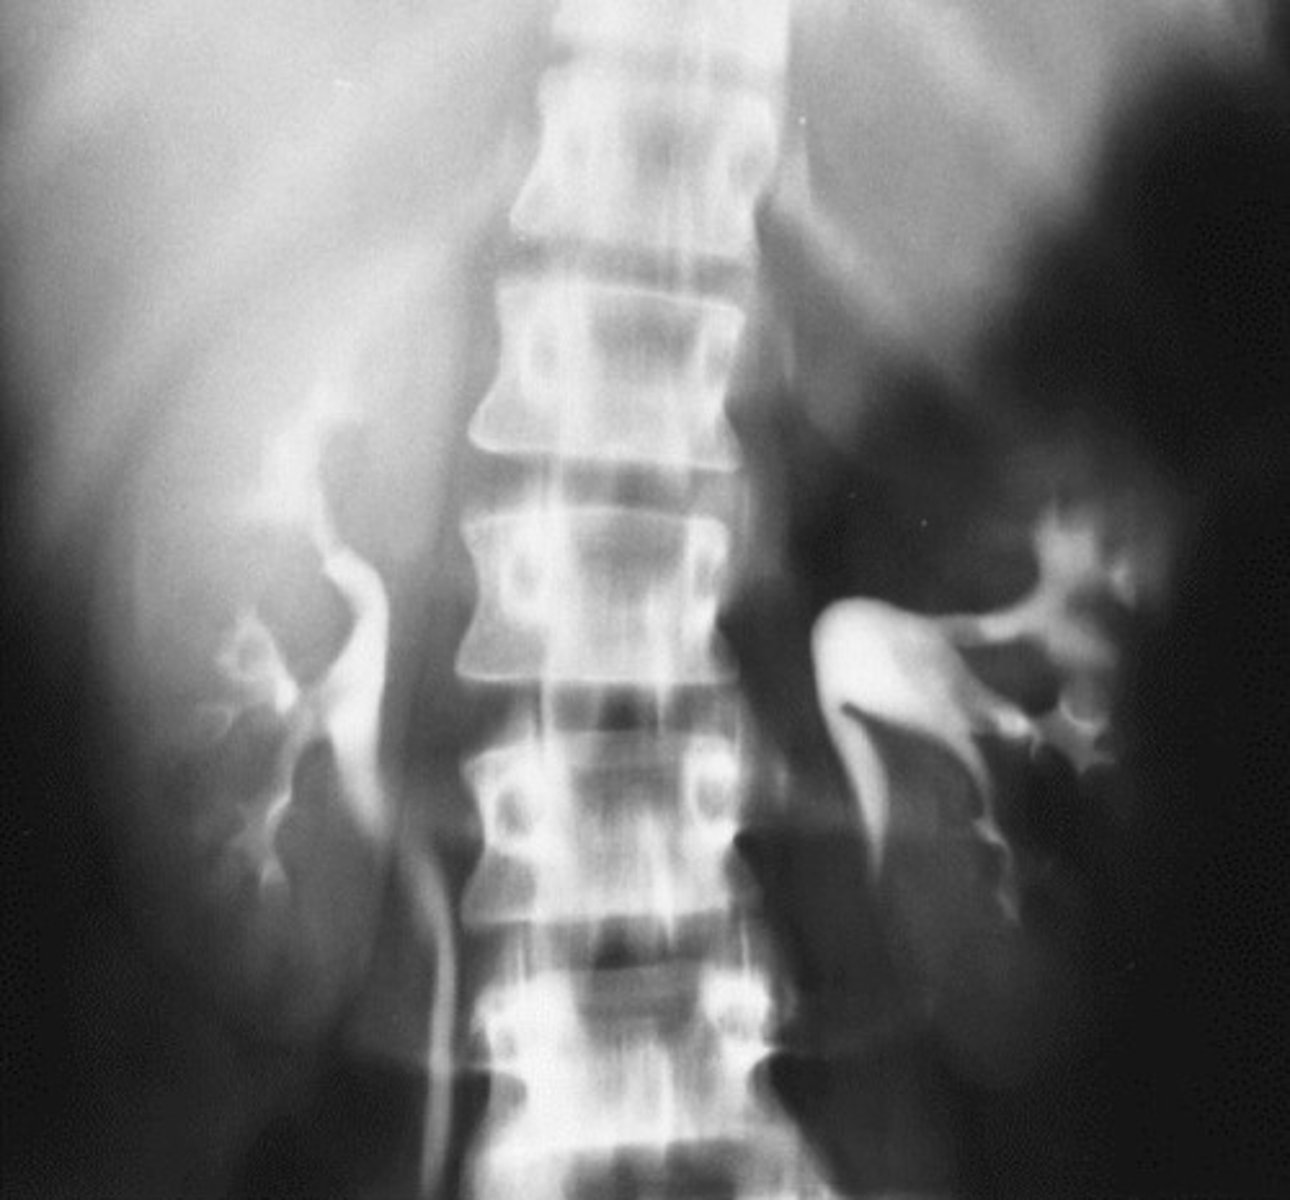

- Malrotation

- Distorted

- What congenital anomaly refers to the kidney being rotated?

- How does this pathology appear radiographically?